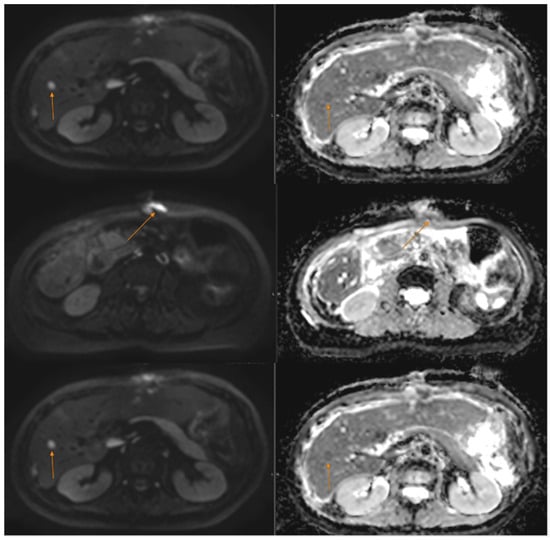

At the time of consultation in our department, the patient’s general health status and biological parameters were excellent. Although the surgery had cytoreductive intent, the postoperative MRI detected residual disease (peri centimetric peritoneal and hepatic metastases)—confirmed by postoperative MRI (see Figure 3). T2W heterogeneous lesions displaying restricted diffusion are observed. These lesions measure 18 × 14 mm on peritoneal surface at the level of liver segments 8–4, 22 × 8 mm and 25 × 10 mm adjacent to each other at the level of segment 2 and 20 × 9 mm adjacent to surgical site on peritoneal surface at the level of segment 6. The patient had a good performance status, no comorbidities, and no contraindications to combined immune-targeted therapy. After multidisciplinary discussion, we opted for treatment with a MET kinase inhibitor (cabozantinib) in combination with a PD-1 checkpoint inhibitor, based on its more favourable safety profile compared to other VEGFR inhibitors such as pazopanib or sunitinib [21]. Furthermore, the NGS panel from the cytoreductive surgery identified PD-L1 expression at 15% TPS, with variants of unknown significance (VUS) in MYC, EWSR1, and STAG2. Given the patient’s prior intolerance and lack of benefit from chemotherapy, first-line targeted therapy combined with immunotherapy was considered a rational and potentially more effective therapeutic option. The combination of cabozantinib, a multi-target tyrosine kinase inhibitor with activity against MET, VEGFR, and AXL, and nivolumab, an immune checkpoint inhibitor targeting PD-1, was selected based on their potential synergistic effect. Cabozantinib may enhance antitumor immunity by modifying the tumour microenvironment, reducing immunosuppressive signalling, and promoting T-cell infiltration, thereby potentiating the efficacy of PD-1 blockade. Although prospective evidence in GNET/CCS is lacking, emerging data in other sarcomas and rare tumours support this strategy as a rational approach in the absence of standard treatment options.

Figure 3. Liver and peritoneal metastases on MRI post-cito-reductive surgery.